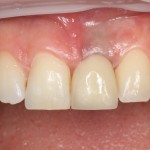

которая через три месяца, к моменту интеграции импланта, выглядит совсем иначе:

Ну и… к моменту установки постоянной коронки, у нас сохранился естественный контур прилегающей десны.

Что, собственно, нам и требовалось сделать.